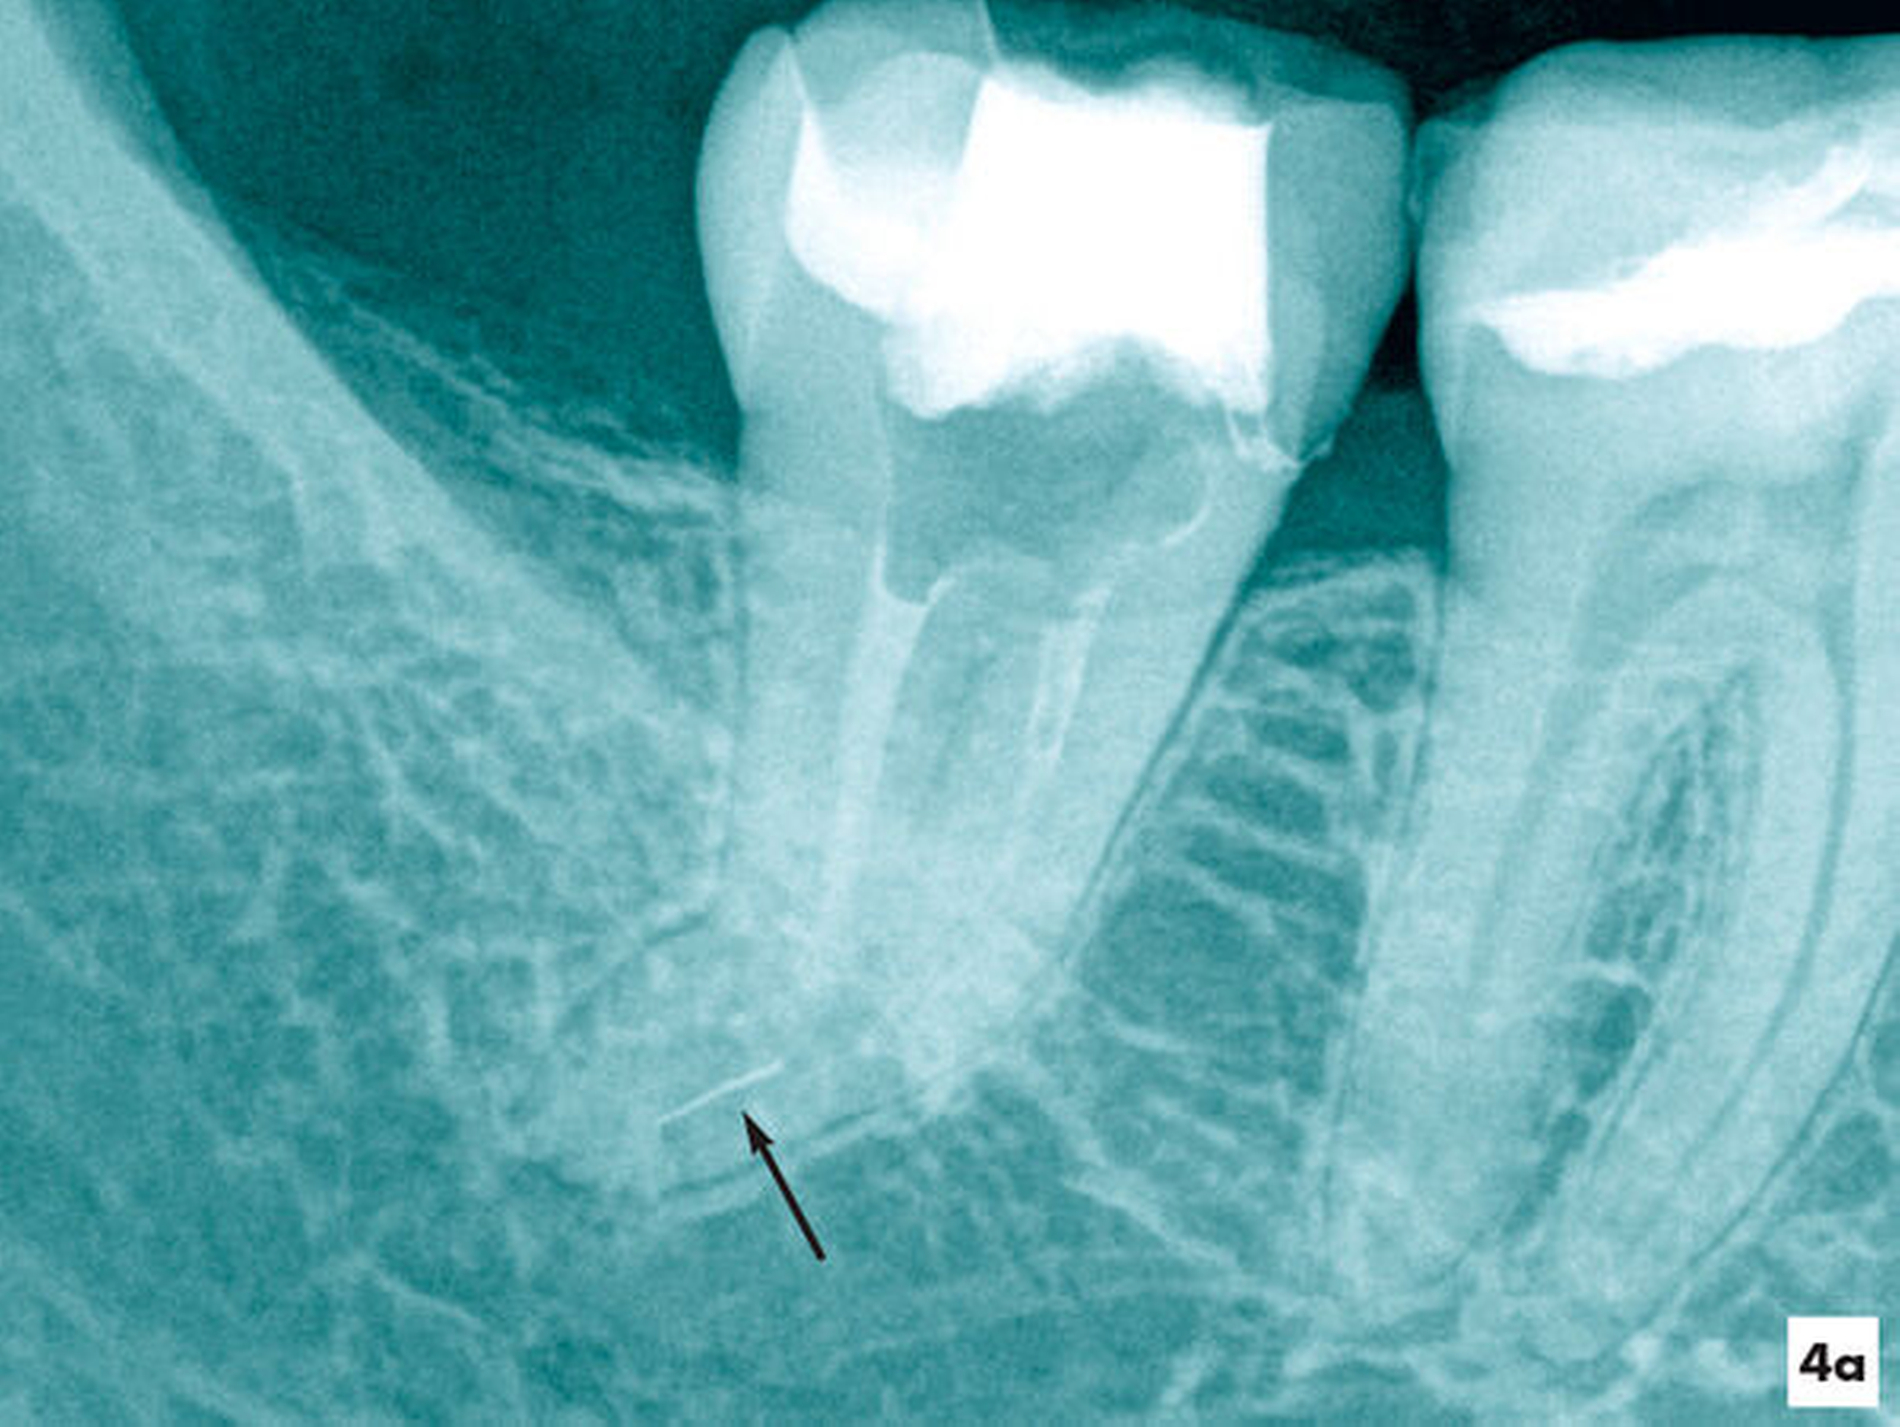

Im Verlauf der Erweiterung eines stark gekrümmten Wurzelkanalsystems kam es nach einer Vitalexstirpation am Zahn 47 zur Fraktur eines Wurzelkanalinstruments in apikaler Lage (Abbildung 4a). Unter Sicht mit dem Dentalmikroskop wurden die Wurzelkanäle bis ins apikale Wurzeldrittel mit NiTi-Feilen bis zum Fragment mechanisch erweitert. Nach einer ultraschallaktivierten Spülung und Desinfektion konnte das Fragment mit einer vorgebogenen Ultraschallfeile IrriK (VDW, München) in der Größe ISO 15 gelockert und entfernt werden, so dass eine vollständige Wurzelkanalbehandlung möglich wurde (Abbildungen 4b und 4c).